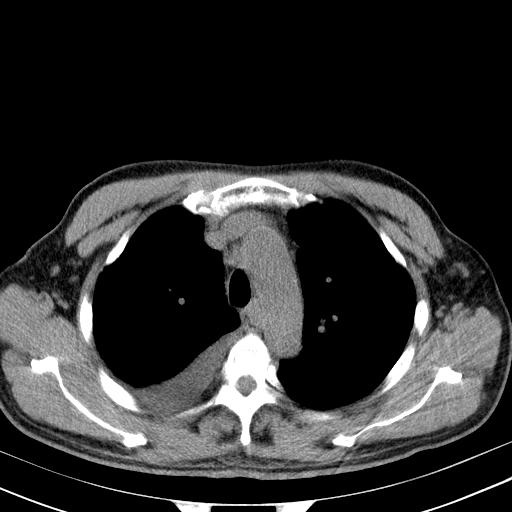

以下是引用zjzjr在2010-3-21 17:39:00的发言:[br]右下中心型肺癌并阻塞性肺炎/不张,纵膈淋巴结肿大,右侧大量胸腔积液,左侧少量胸腔积液

以下是引用zxl51642在2010-3-21 17:06:00的发言:[br]右下中心型肺癌并阻塞性肺炎/不张,纵膈淋巴结肿大,右侧大量胸腔积液,左侧少量胸腔积液,少量腹水。建议纤维支气管镜进一步检查。